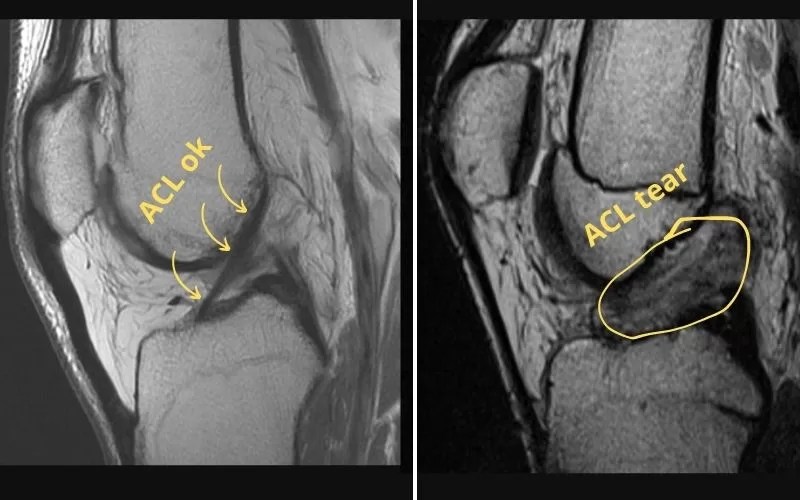

How To Diagnose An Acl Tear . A healthcare provider will diagnose an acl tear with a physical exam and some tests. The most common symptoms of an acl tear include: The lachman test is the most accurate test for detecting an acl tear. Severe pain is one of the most common. Magnetic resonance imaging is the primary study used to diagnose acl injury in the united states. The patient is typically unable to return to the ongoing. Mri is the primary modality to diagnose acl pathology, with a sensitivity of 86% and a specificity of 95%. If you hear a pop coming from your knee at the time of the injury, it may be a tear. Diagnosis may also be made with knee arthroscopy to differentiate complete from. They’ll ask you about your symptoms and look at your knee. Anterior cruciate ligament injury is typified by a sudden, painful, audible pop noise. Diagnosis can be suspected clinically with presence of a traumatic knee effusion with increased laxity on lachman's test but requires mri studies to confirm diagnosis.

The patient is typically unable to return to the ongoing. Mri is the primary modality to diagnose acl pathology, with a sensitivity of 86% and a specificity of 95%. If you hear a pop coming from your knee at the time of the injury, it may be a tear. Diagnosis may also be made with knee arthroscopy to differentiate complete from. They’ll ask you about your symptoms and look at your knee. Magnetic resonance imaging is the primary study used to diagnose acl injury in the united states. Anterior cruciate ligament injury is typified by a sudden, painful, audible pop noise. Severe pain is one of the most common. Diagnosis can be suspected clinically with presence of a traumatic knee effusion with increased laxity on lachman's test but requires mri studies to confirm diagnosis. The lachman test is the most accurate test for detecting an acl tear.